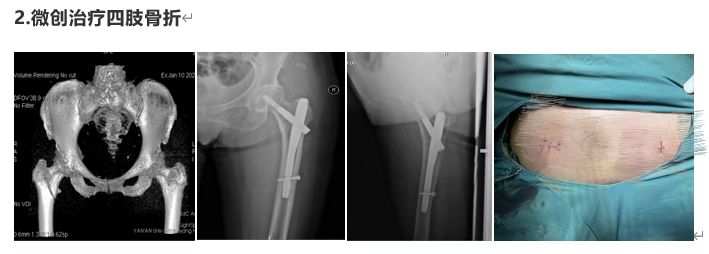

部分病例展示